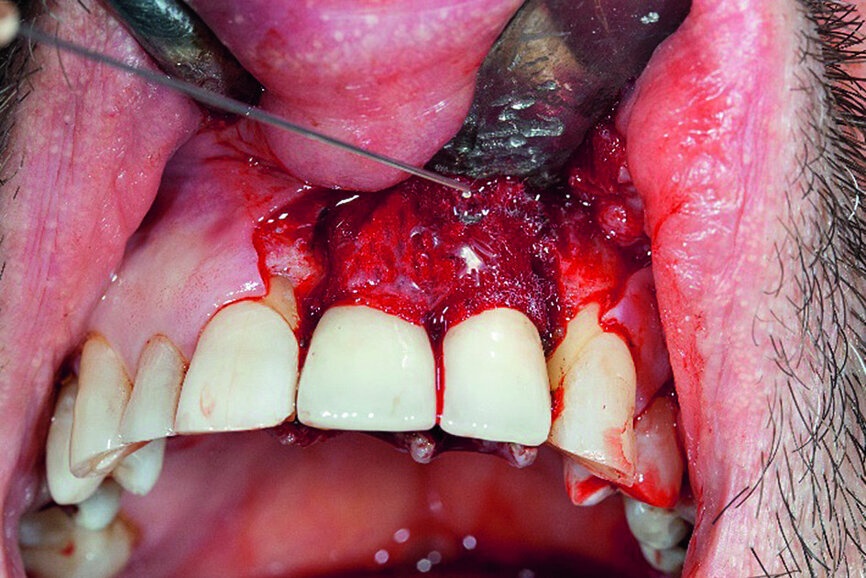

A 59-year-old patient presented to the practice complaining about minor exudate at his dental implants in the anterior region (Fig. 1). Probing revealed a deep circular pocket around the implants during the initial examination. Mobility of the implants was, however, not detected. As suspected, the radiographic examination confirmed an advanced peri-implantitis at the recently placed implants (Fig. 2).

In accordance with the described protocol, a mucoperiosteal flap was created in order to obtain full access to the severe four-wall defect (Fig. 3). The implant surface was mechanically cleaned with diamond-coated burs (Fig. 4). Chemical debridement of the surface with subsequent antibiotic impregnation was performed (Figs. 5 & 6).